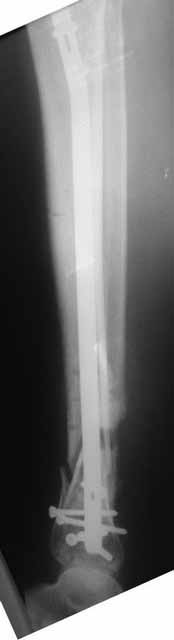

Примерная ситуация. Пациент 37 лет. Синтезировали где-то пластинкой. Попал к нам через 2 месяца.

19 апреля убрали через проколы пластину с винтами, пересекли fibula, наложили аппарат.

Немного потянули по оси, убрали вальгус, ротацию. 22 апреля (на 3-е сутки) заштифтовали окончательно. 29 апреля выписали из отделения. На все ушло 10 дней.

С уважением, Никита Заднепровский